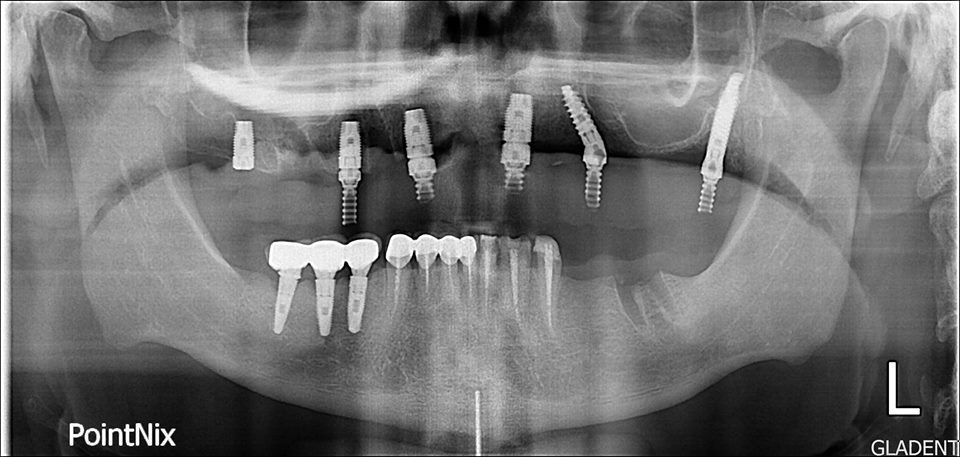

| КТ до имплантов |

КТ после

имплантации |